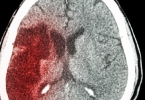

脑组织受损面积直接影响恢复周期。腔隙性梗死病灶直径小于15毫米患者通常在1-3个月内功能基本恢复,而多发小梗死灶可能延长至6个月。影像学检查显示的缺血半暗带区域越大,神经功能代偿所需时间越长。